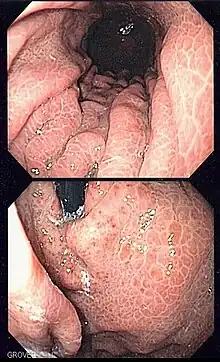

| Image of portal hypertensive gastropathy seen on endoscopy of the stomach. The normally smooth mucosa of the stomach has developed a mosaic like appearance, that resembles snake-skin. | |

Portal hypertensive gastropathy refers to changes in the mucosa of the stomach in patients with portal hypertension; by far the most common cause of this is cirrhosis of the liver. These changes in the mucosa include friability of the mucosa and the presence of ectatic blood vessels at the surface. Patients with portal hypertensive gastropathy may experience bleeding from the stomach, which may uncommonly manifest itself in vomiting blood or melena; however, portal hypertension may cause several other more common sources of upper gastrointestinal bleeding, such as esophageal varices and gastric varices. On endoscopic evaluation of the stomach, this condition shows a characteristic mosaic or "snake-skin" appearance to the mucosa of the stomach.

The diagnosis of portal hypertensive gastropathy is usually made on endoscopy. The usual appearance of portal hypertensive gastropathy on endoscopy is a mosaic-like or reticular pattern in the mucosa. Red spots may or may not be present. The pattern is usually seen throughout the stomach.[2] A similar pattern can be seen with a related condition called gastric antral vascular ectasia (GAVE), or watermelon stomach. However, in GAVE, the ectatic blood vessels are more commonly found in the antrum or lower part of the stomach.[2]